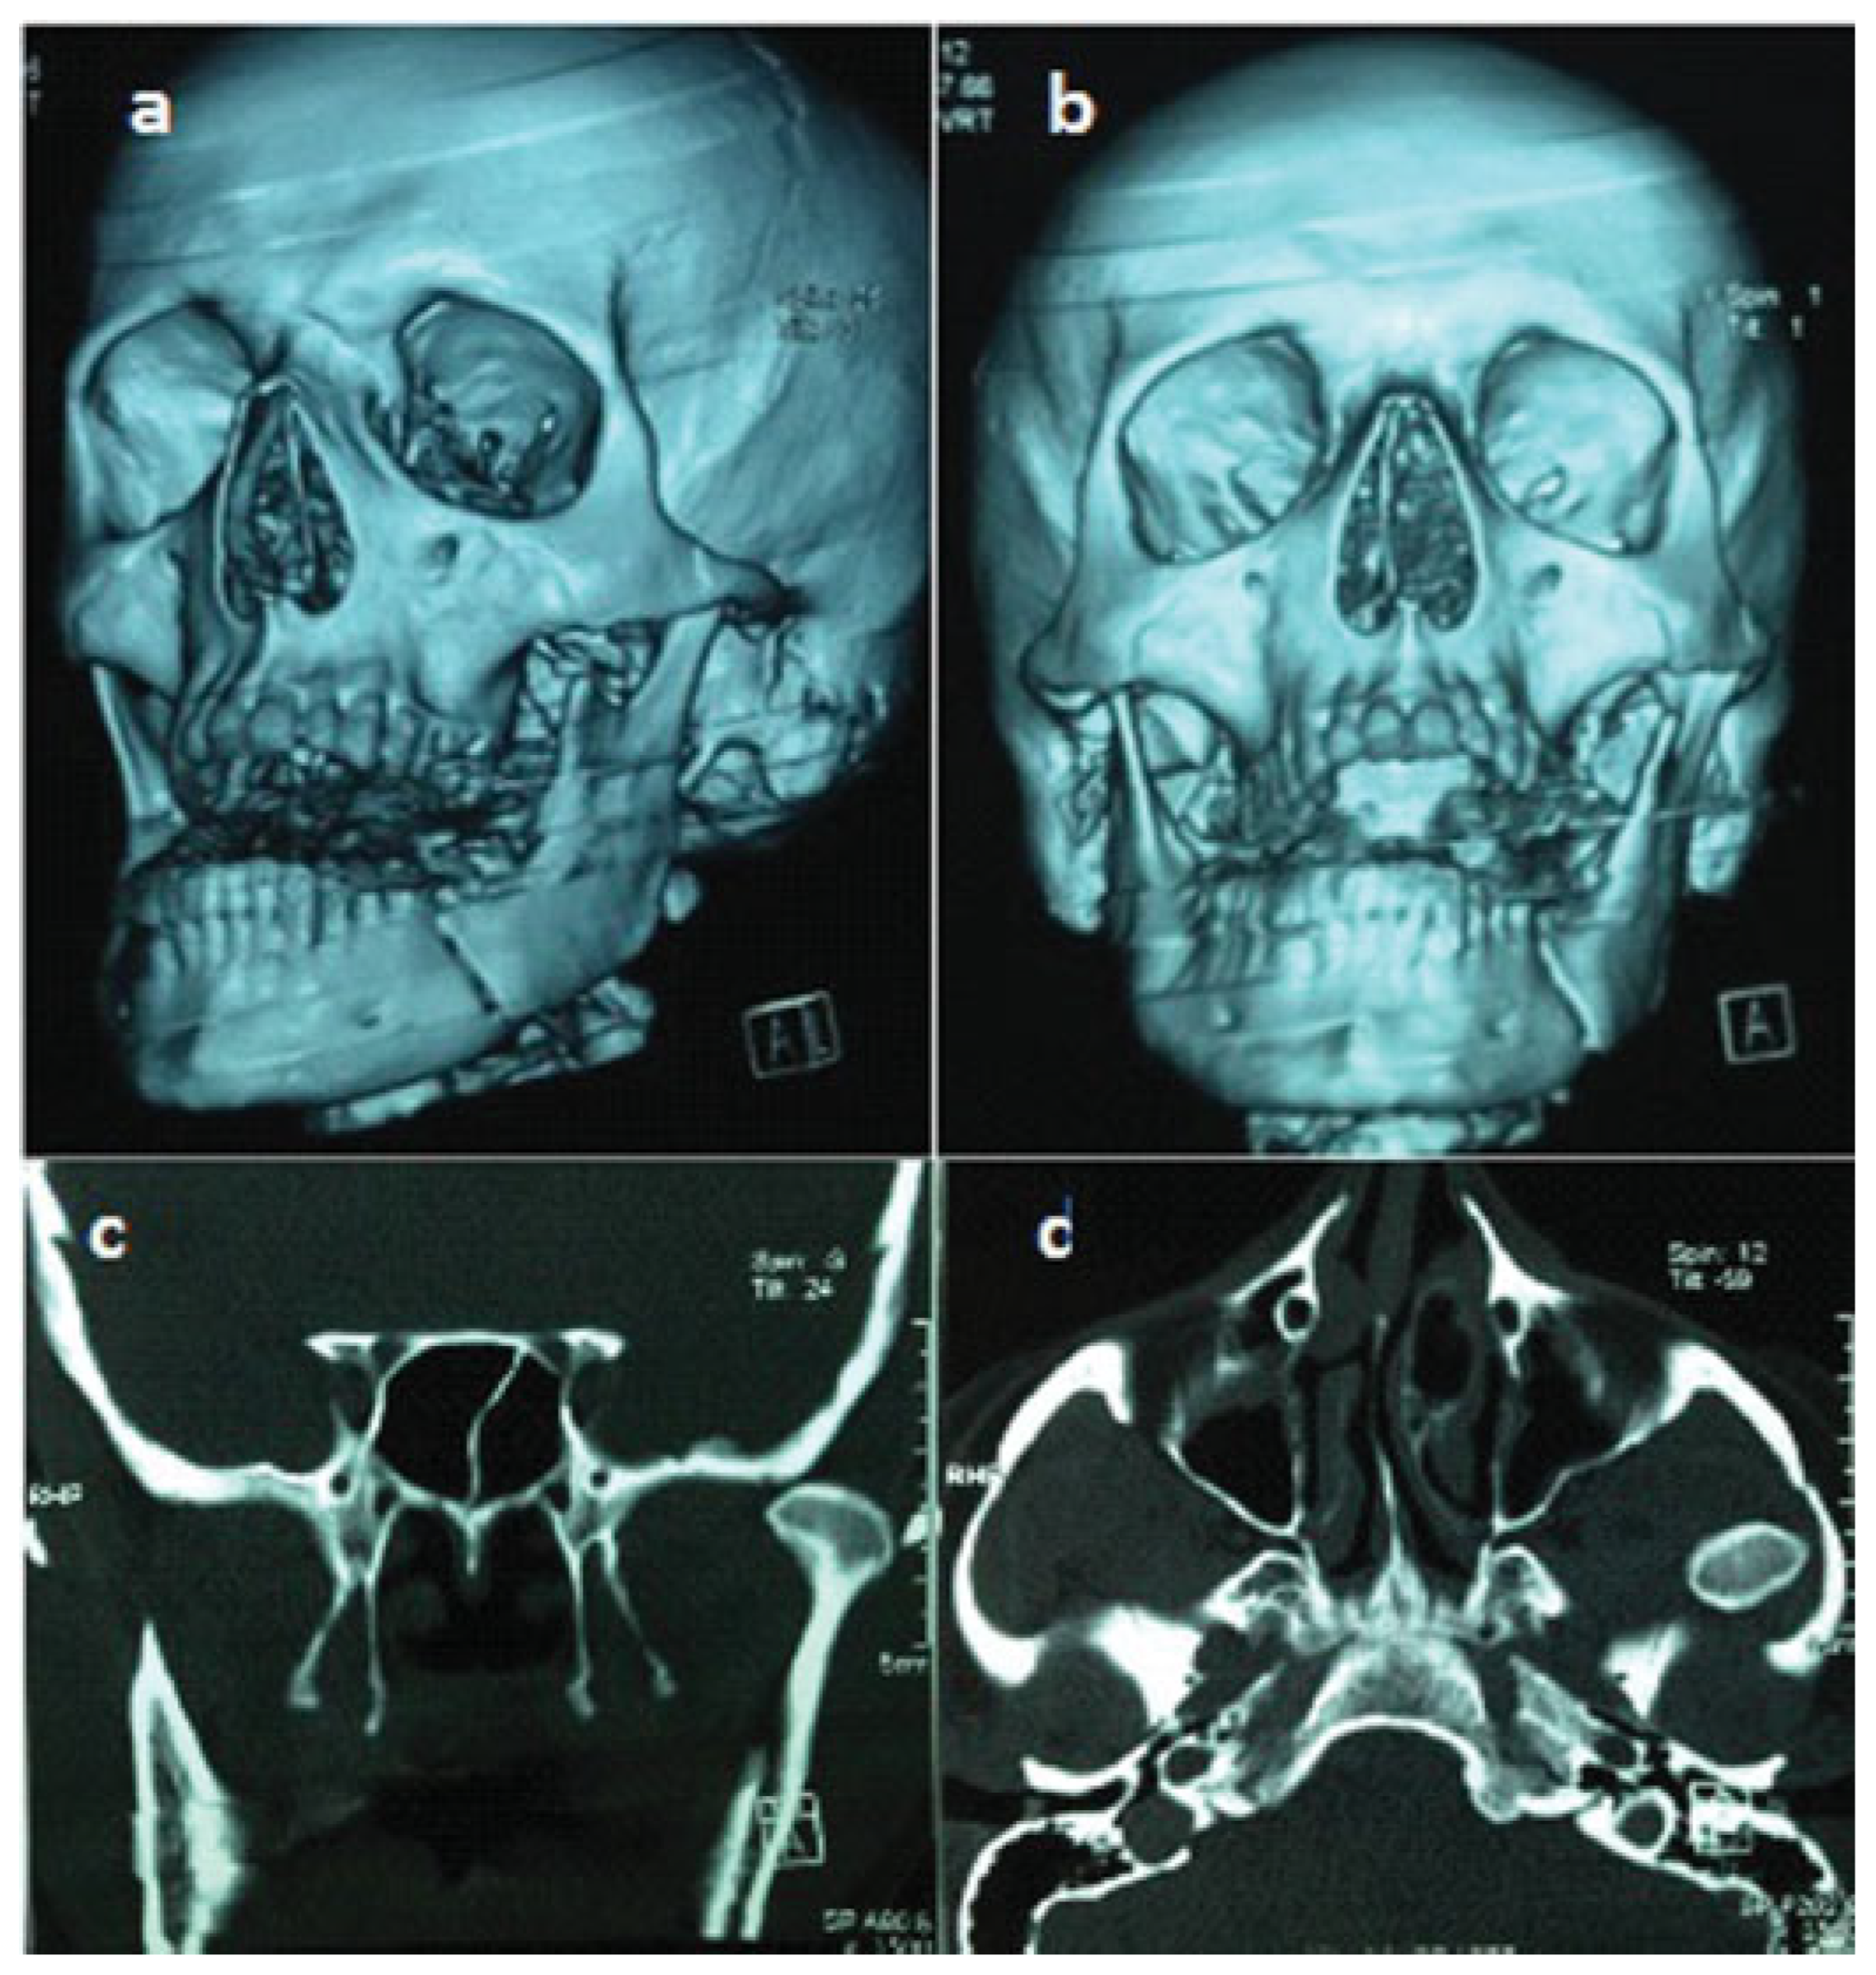

Traumatic Anterosuperior Dislocation of the Intact Mandibular Condyle into the Temporal Fossa

:Case Report